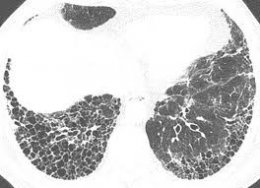

Интерстициальные заболевания легких

Интерстициальные заболевания представляют собой воспалительные процесса в соединительных тканях (кровеносных сосудах, альвеолах). При этом происходит сдавливание альвеол, они замещаются соединительной тканью, образуется фиброз.

Примерно половина подобных случаев имеет неизвестную природу, эти формы получили названия фиброзирующего альвеолита, синдрома Хаммана-Рича, легочного фиброза. Читать далее